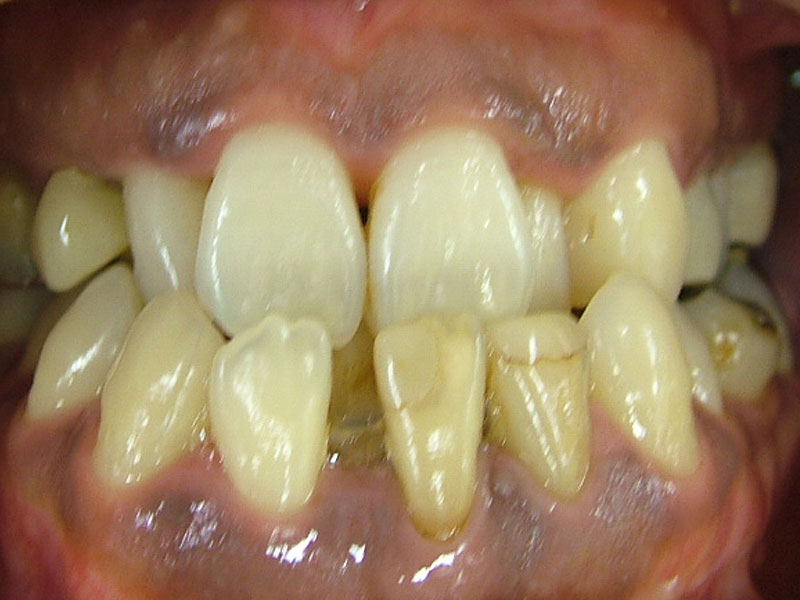

術前

- 初診:2006年。2010年―矯正治療を含めた一口腔単位の治療開始、治療当時、30代女性、喫煙者

- 主訴:虫歯治療、歯周病治療、できれば歯並びも治したい。

- 矯正診断:3級骨格性の反対咬合

- 治療方針:以前に治療した歯の再治療(虫歯治療、歯内療法、歯周処置)、右下前歯1本抜歯、矯正用インプラントを用いたワイヤー矯正、修復処置(被せ物)、保定(上ワイヤー、下マウスピース)、歯茎のピーリング(漂白)、4か月メンテナンス